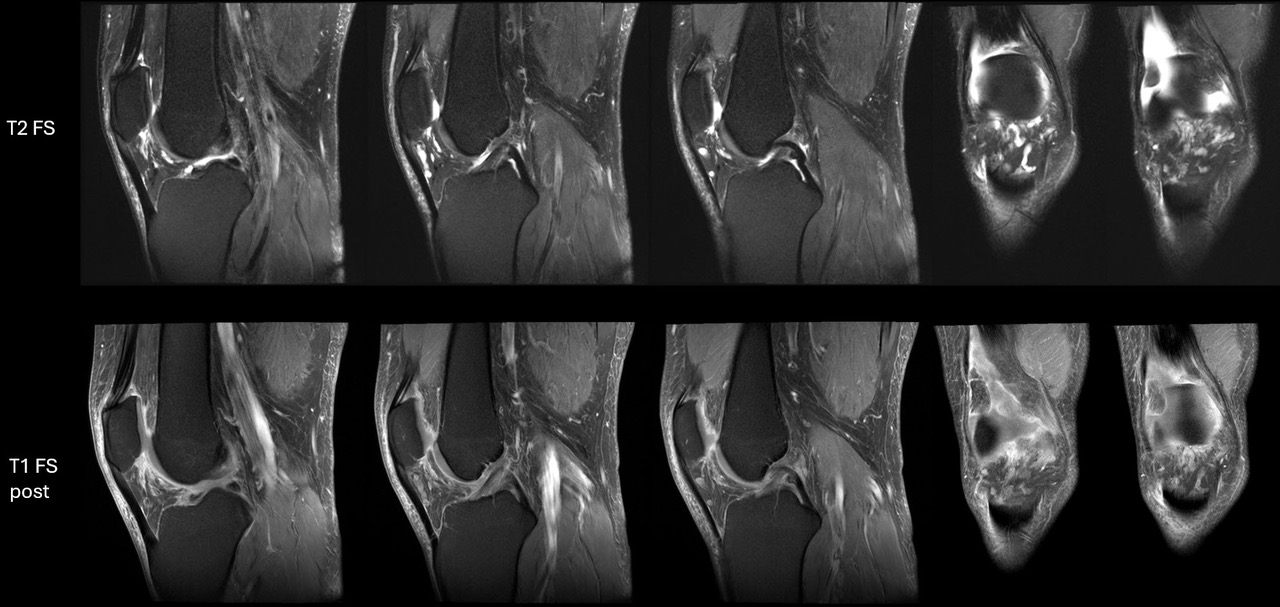

Here is a companion case from San Diego. 50-year-old man.with tubular masses in both Hoffa’s fat pads. They weren’t present on bilateral knee MRI exams from 10 years prior, but since then he has had 11 high molecular weight HA injections – all bilateral, done without image-guidance. We brought him back for post-contrast imaging and the lesions showed slow, gradual enhancement. His right knee images are attached, and like your case, the findings were essentially identical on the other side.

I think our cases fall in the spectrum of chronic granulomatous foreign body reactions, which was nicely summarized in a recent case report in Skeletal Radiology (https://doi.org/10.1007/s00256-024-04824-y). Reactive vascular channels have been seen in these lesions (https://doi.org/10.2106/jbjs.d.02436), and these may be so prominent that they can mimic a low flow vascular malformation (https://doi.org/10.1016/j.radcr.2023.10.007).